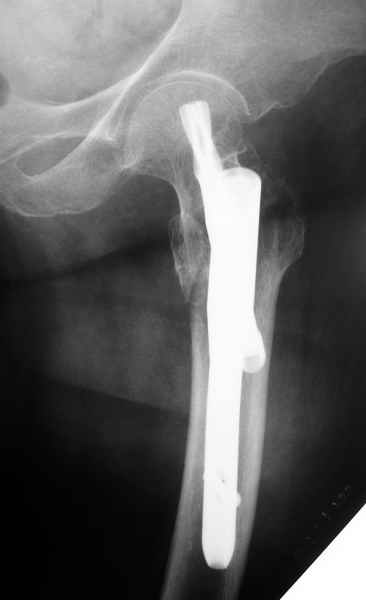

Другие случаи: применение Synthes TTFN (trochanteric titanium femoral nail) и Blade Plate (угловая пластина), так что много различных вариантов фиксации подобных переломов.